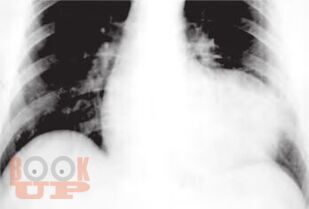

Методика обследования кардиохирургического больного перед операцией на сердце

Общая методика обследования больного известна выпускникам медицинского вуза. Однако в каждой специальности имеются вопросы, для ответа на которые применяются дополнительные методы исследования. Пациенты, готовящиеся к операции на сердце, требуют особого подхода ввиду сложности патологии и высокого риска возникновения угрожающих жизни осложнений. Чтобы не упустить важную информацию, необходимо знать специфику кардиохирургической патологии и тот оптимальный набор исследований, который позволит предусмотреть возможные риски. Методические рекомендации по ведению пациентов с показаниями к операции отражены в настоящем издании.